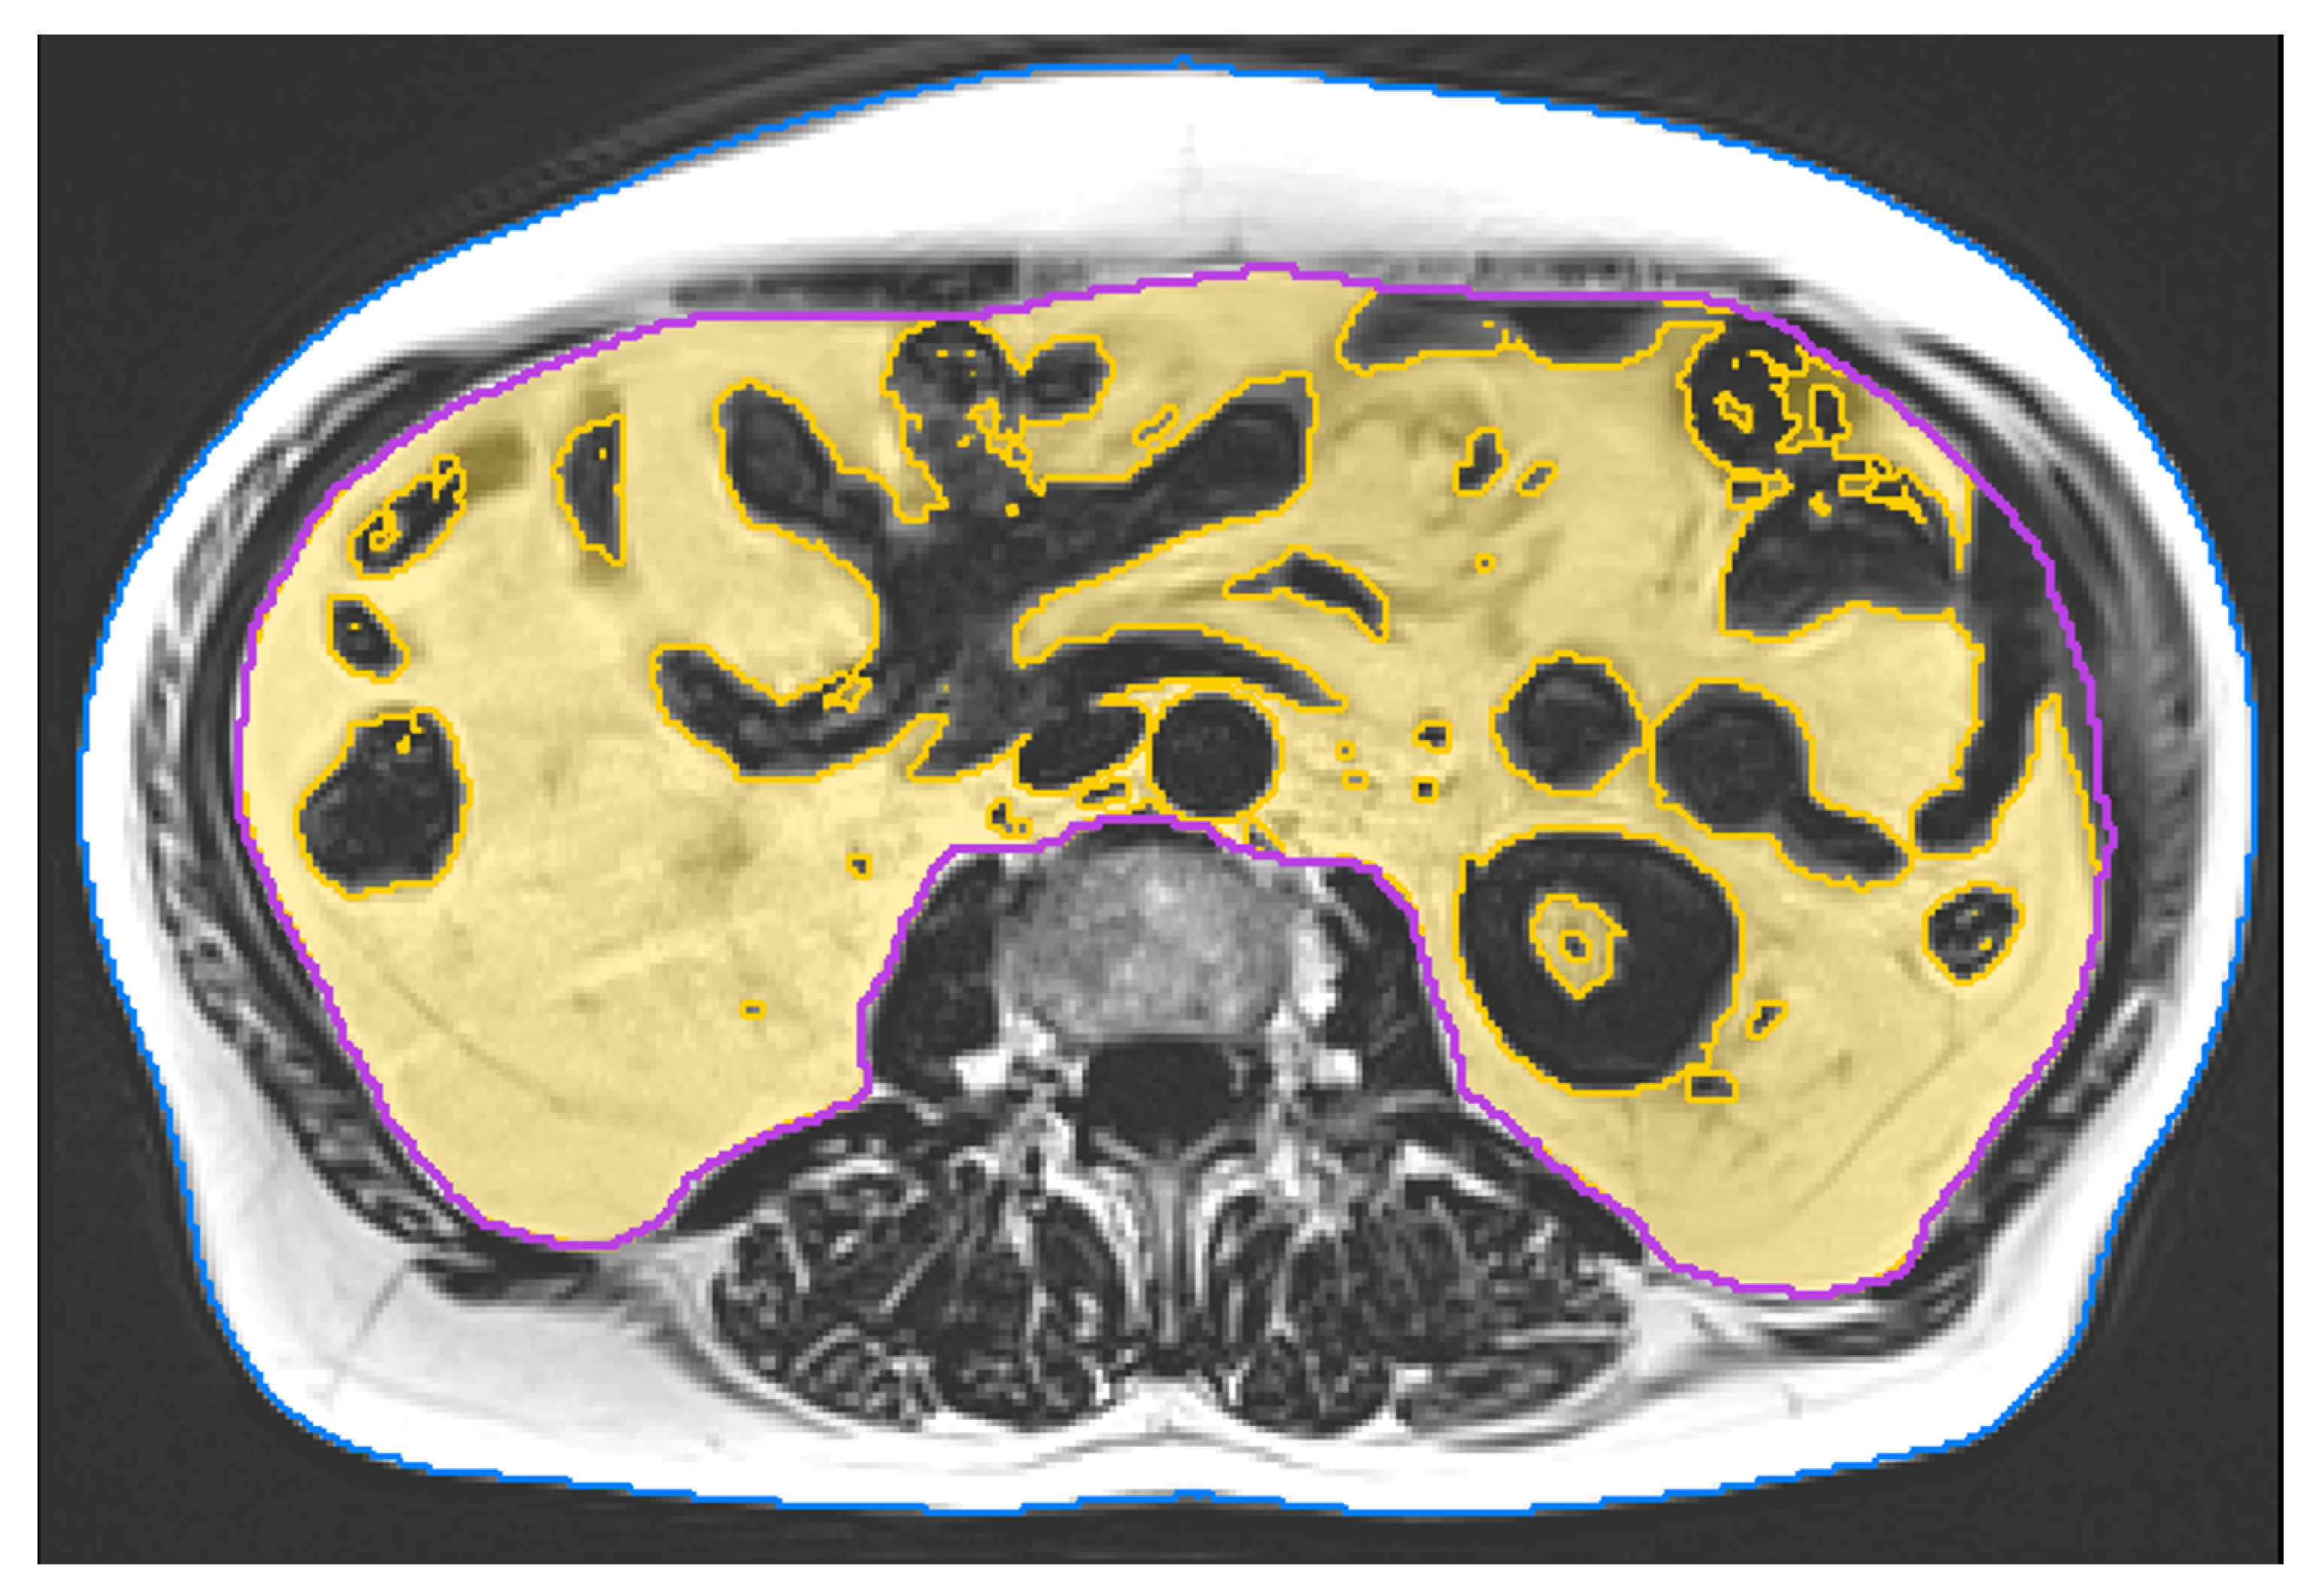

MRI scans were acquired at baseline and after 29 weeks of intervention. All scans were consistently acquired on a 3 Tesla scanner (PRISMA, Siemens Healthineers, Erlangen, Germany). We applied a non-contrast enhanced 2-point Dixon Gradient Echo Volumetric Interpolated Breath-hold Examination (VIBE) sequence (TE: 1.29 ms; TR: 3.97 ms; matrix size: 320x260; voxel size: 1.2×1.2x3.5 mm3; slice gap: 0.7 mm). Twelve slices covered a total length of approximately 5 cm from mid L2 to mid L3. Image analysis was performed using MIAF (Medical Image Analysis Framework, Friedrich-Alexander-University of Erlangen-Nürnberg) as described in detail in a previous publication [26]. The first and last slice were left out due to intensity inhomogeneity. In the remaining ten slices, the outer contour of the body was determined automatically. The contour of the abdominal cavity was manually segmented by a supervised and trained research assistant. This was performed slice by slice using open source software Fiji [27]. Between both measurements of a participant, the position of the scanned volumes was evaluated and non-overlapping slices were cut off if necessary. In order to separate VAT inside the abdominal cavity from inner organs such as kidneys or intestines, and blood vessels, we used a threshold calculated by the Otsu Method [28] (Figure 2).

Figure 2. Final segmentation result of VAT (yellow overlay) without inner organs and intestines; inner abdominal volume (magenta contour); and outer contour of the body (blue).